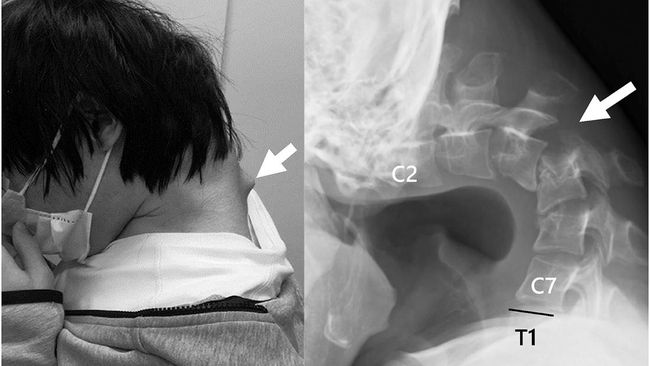

Leher Pria Bengkok gegara Keseringan Main Game di Ponsel (Foto: JOS Case Reports)

Selama masa isolasi tersebut, pasien menghabiskan waktu berjam-jam bermain game di ponsel dengan posisi leher yang menunduk secara ekstrem. Kebiasaan ini berlangsung lama hingga berdampak pada struktur tulang lehernya.

Hasil pemindaian CT menunjukkan bahwa sejumlah ruas tulang lehernya mengalami distorsi dan pergeseran. Selain itu, jaringan menyerupai jaringan parut terbentuk di sepanjang tulang belakang, memperburuk kondisi lehernya.

Para ahli menyimpulkan bahwa sindrom kepala jatuh yang dialami pasien tersebut disebabkan oleh kombinasi antara postur menunduk ekstrem dalam jangka panjang saat bermain ponsel, serta gangguan perkembangan akibat trauma psikologis yang dialami pada masa remaja.

Sindrom kepala jatuh atau dropped head syndrome merupakan kondisi medis yang ditandai dengan kelemahan parah pada otot-otot leher, sehingga kepala tidak dapat ditopang secara normal. Meski umumnya dikaitkan dengan penyakit neuromuskular, kondisi ini dapat pula dipicu oleh penyebab lain.